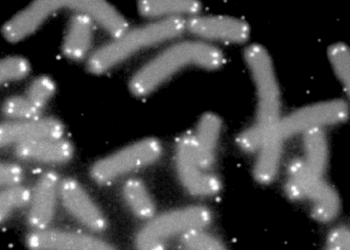

Father loss associated with shorter child telomere length

1. Any father loss, or loss of father by death, separation and/or divorce, or incarceration was associated with a significant ...